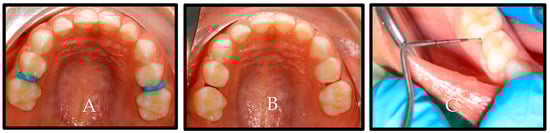

The findings of the radiographic scores obtained by both the experimental and control groups at the baseline and the 6- and 12-month follow-up visits exhibited a tendency that was comparable to that observed in the ICDAS II; nevertheless, there was no statistically significant difference between the two groups in the radiographic scores at the baseline and follow-up visits. Figure 4 is an illustration of the lesion evaluation using radiographs.

Figure 4. Bitewing radiographs of the same patient at the baseline and after 12 months. (A): #55 (control) at the baseline mesial carious lesion (E1). (B): #65 (experimental) at the baseline mesial carious lesion (E2). (C): #55 (control) after 12 months mesial carious lesion showing slight progression (D1). (D): #65 (experimental) after 12 months mesial carious lesion without progression (E2).